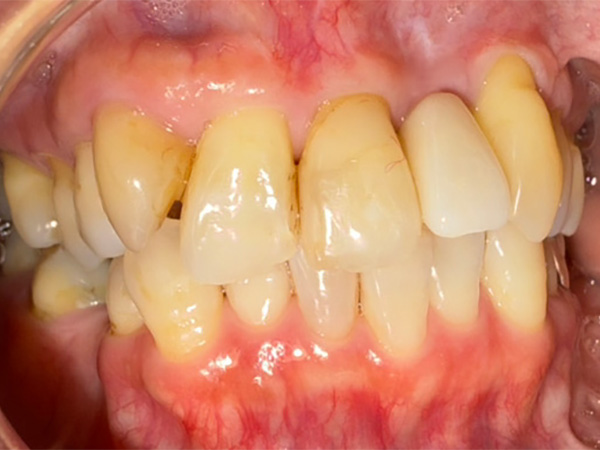

インプラント症例その1

術後

④ 治療内容(一般的な流れ)

1. 診査・診断(問診、視診、口腔内診査、レントゲン、CT等)

2. 治療計画の説明

3. インプラントガイドの指摘、口腔内清掃

4. 局所麻酔下でのインプラント体埋入手術(一次オペ)

5. 治癒期間(数か月)

6. 二次オペ(局所麻酔下で、歯肉を切開してインプラント体にヒーリングアバットメントと呼ばれるキャップをセットする治療。この治療をすることでインプラント体に人工歯をつけることができる。一次オペでインプラント体と骨がしっかりと固定できていれば、一次オペと同時にすることもある治療)

7. 治癒期間(1ヶ月から2ヶ月)

8. 人工歯作成のための印象採得

9. 人工歯装着

10. 約1週間後に噛み合わせのチェック

11. 定期的なメンテナンス